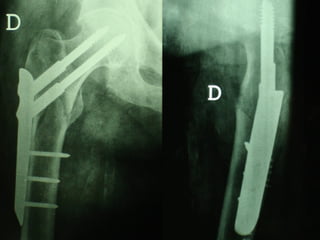

Dal Gennaio 2000 al Dicembre 2005 27 placche LISS di femore

Stabilità tramite attrito placca    osso

Osso porotico Stabilità con viti autobloccate

INDICAZIONI COMUNI Fratture sovracondiloidee Fratture intercondiliodee Fratture diafisarie distali PARTICOLARI Fratture con grave osteoporosi Fratture periprotesiche

VANTAGGI CHIRURGIA MININVASIVA Mini Open Inserimento della placca sottocutaneo per scivolamento Viti percutanee Preservazione dei tessuti molli Ridotto danno vascolare Rapida ripresa funzionale

F, 68 y

LISS  NCB

NCB